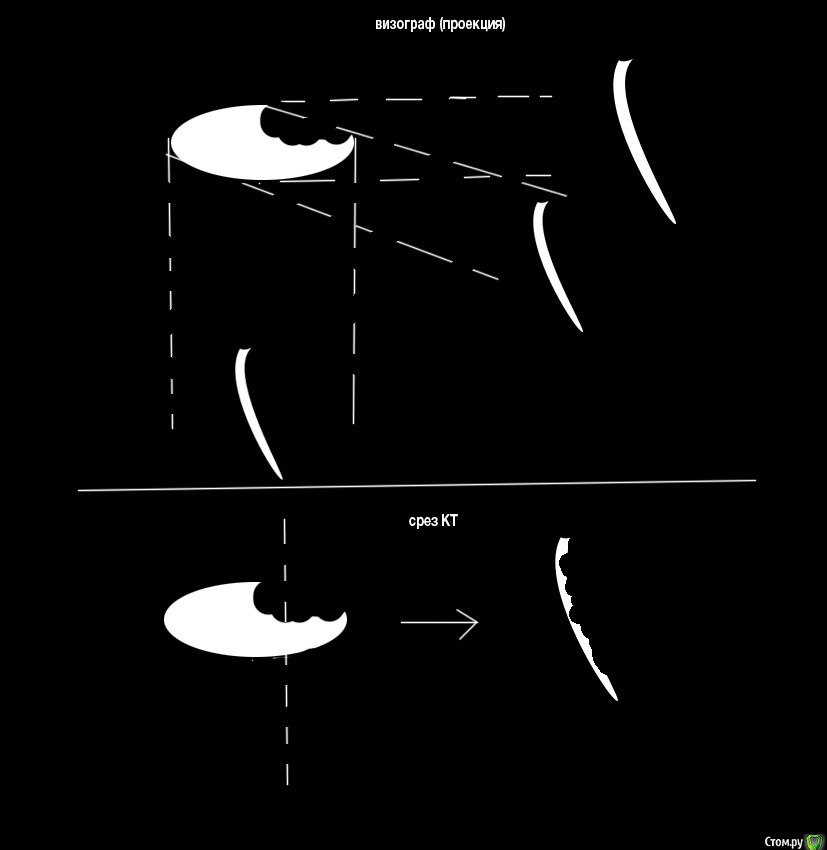

bestlion Опубликовано 21 мая, 2017 Автор Поделиться Опубликовано 21 мая, 2017 Значит не о какой постоянной пломбе не может быть и речи, только коронка. 0.5 мм до ренгенологичекской верхушки это норма. если вы беспокоетесь что возможно не все хорошо будет, вы можете перейти на полгода на временную коронку, делая снимки в динамике, если есть улучшения переходите к постоянной конструкции (коронке). и Приложите прицельные снимки в разных проекциях так будет четче видно.вы не объяснили почему, но полагаю из за большой полости и риска трещины ?я совсем не "фанат" коронок, из за невозможности визуально контролировать состояние зуба, а суммарную вероятность всяческих отклонений и развитие кариеса под коронкой я считаю выше чем риск трещины, по крайней мере в данном случае (когда цело >50% поверхности). Субъективно из личного опыта и опыта окружения - чем меньшей площади коснулся бур - тем живее зуб.Я вообще не совсем понимаю почему стоматологи вместо расчета давления на зуб и установки "креативной" пломбы предоставляют только выбор "клин" или коронкавот так навскидку, на примере моего зуба: кроме этого есть какие-то новые материалы (как я понимаю хорошая агдезия к дентину и эмали и достаточная прочность)https://www.youtube.com/watch?v=0Sf4DSM4XkI ----------------------------------------------------------------------- Однако в данный момент меня больше беспокоит нормально ли запломбирован канал (можно ли оставить "как есть") или нужно перелечивать Приложите прицельные снимки в разных проекциях пока таких нет, только завтра смогу сделать..вы имеете ввиду визографом? им же никак не снять проекцию поперечно зубному ряду?и стенки канала на КТ не выглядят овальными, а на продольной все же сливается в одну линиючто я имею ввиду: Ссылка на комментарий